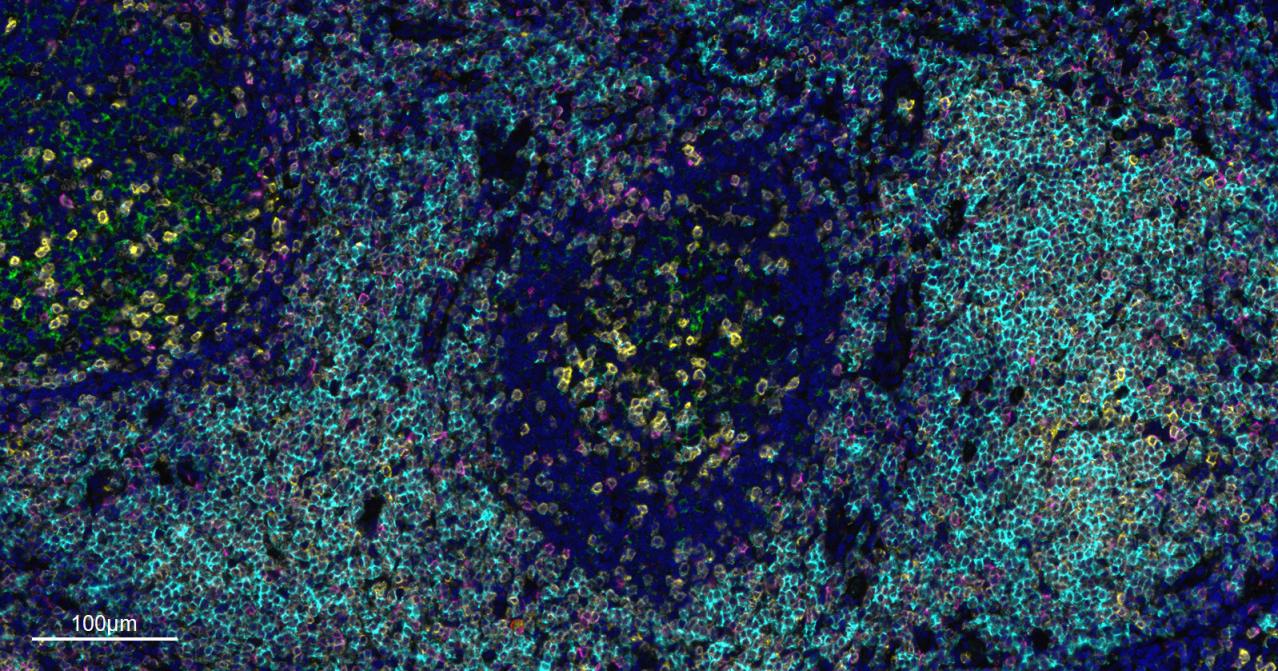

Immunology > Adaptive Immunity > Regulatory T Cells

Immunology > Adaptive Immunity > T Cells > CD

Stem Cells > Hematopoietic Progenitors > Lymphoid > T Lymphocytic Lineage

Stem Cells > Hematopoietic Progenitors > Myeloid > Dendritic Cell Lineage

Stem Cells > Hematopoietic Progenitors > Myeloid > Monocytic Lineage

| mIHC | Human | 1:100-500 |